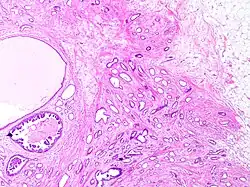

Tubular carcinomas are generally around 1 cm. or smaller, and are made up of tubules. They are usually low-grade.[2] Elastosis has been noted as common but is not present in all cases.[11]

A highly differentiated invasive carcinoma that forms well-defined tubules (containing epithelium, but no myoepithelium) and that have abundant desmoplastic fibrous stromal reaction between the tubules.